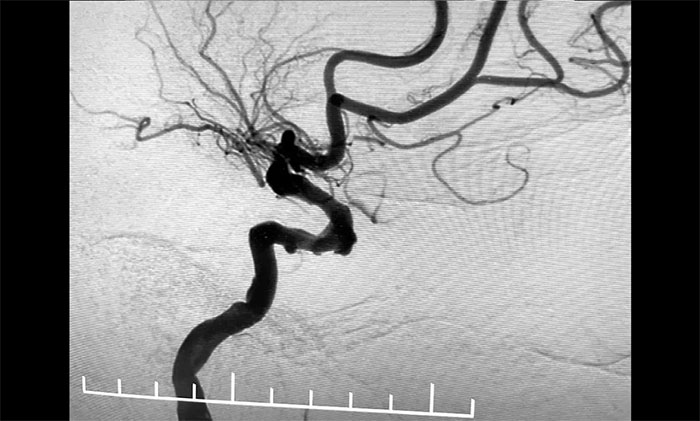

▲ 颈动脉狭窄合并左颈内动脉海绵窦段、床突段多发动脉瘤

接下来,左颈内动脉海绵窦段、床突段多发动脉瘤处理极具挑战。由于C5、C6、C7段血管极度迂回曲折,类似“N”形,从C4、C5到C6之间的血管约成45°锐角,从C6至C7之间又是约30°锐角,可谓“山路十八弯”,而导丝又是极软,每向前推进一毫米,都非常艰难。这种介入手术对术者的技术要求非常高,如果支架贴合不好,打开不良,还需要用导丝蠕动“按摩”,让支架重新回到血管壁上。

▲ 血管极度迂曲,为手术带来挑战